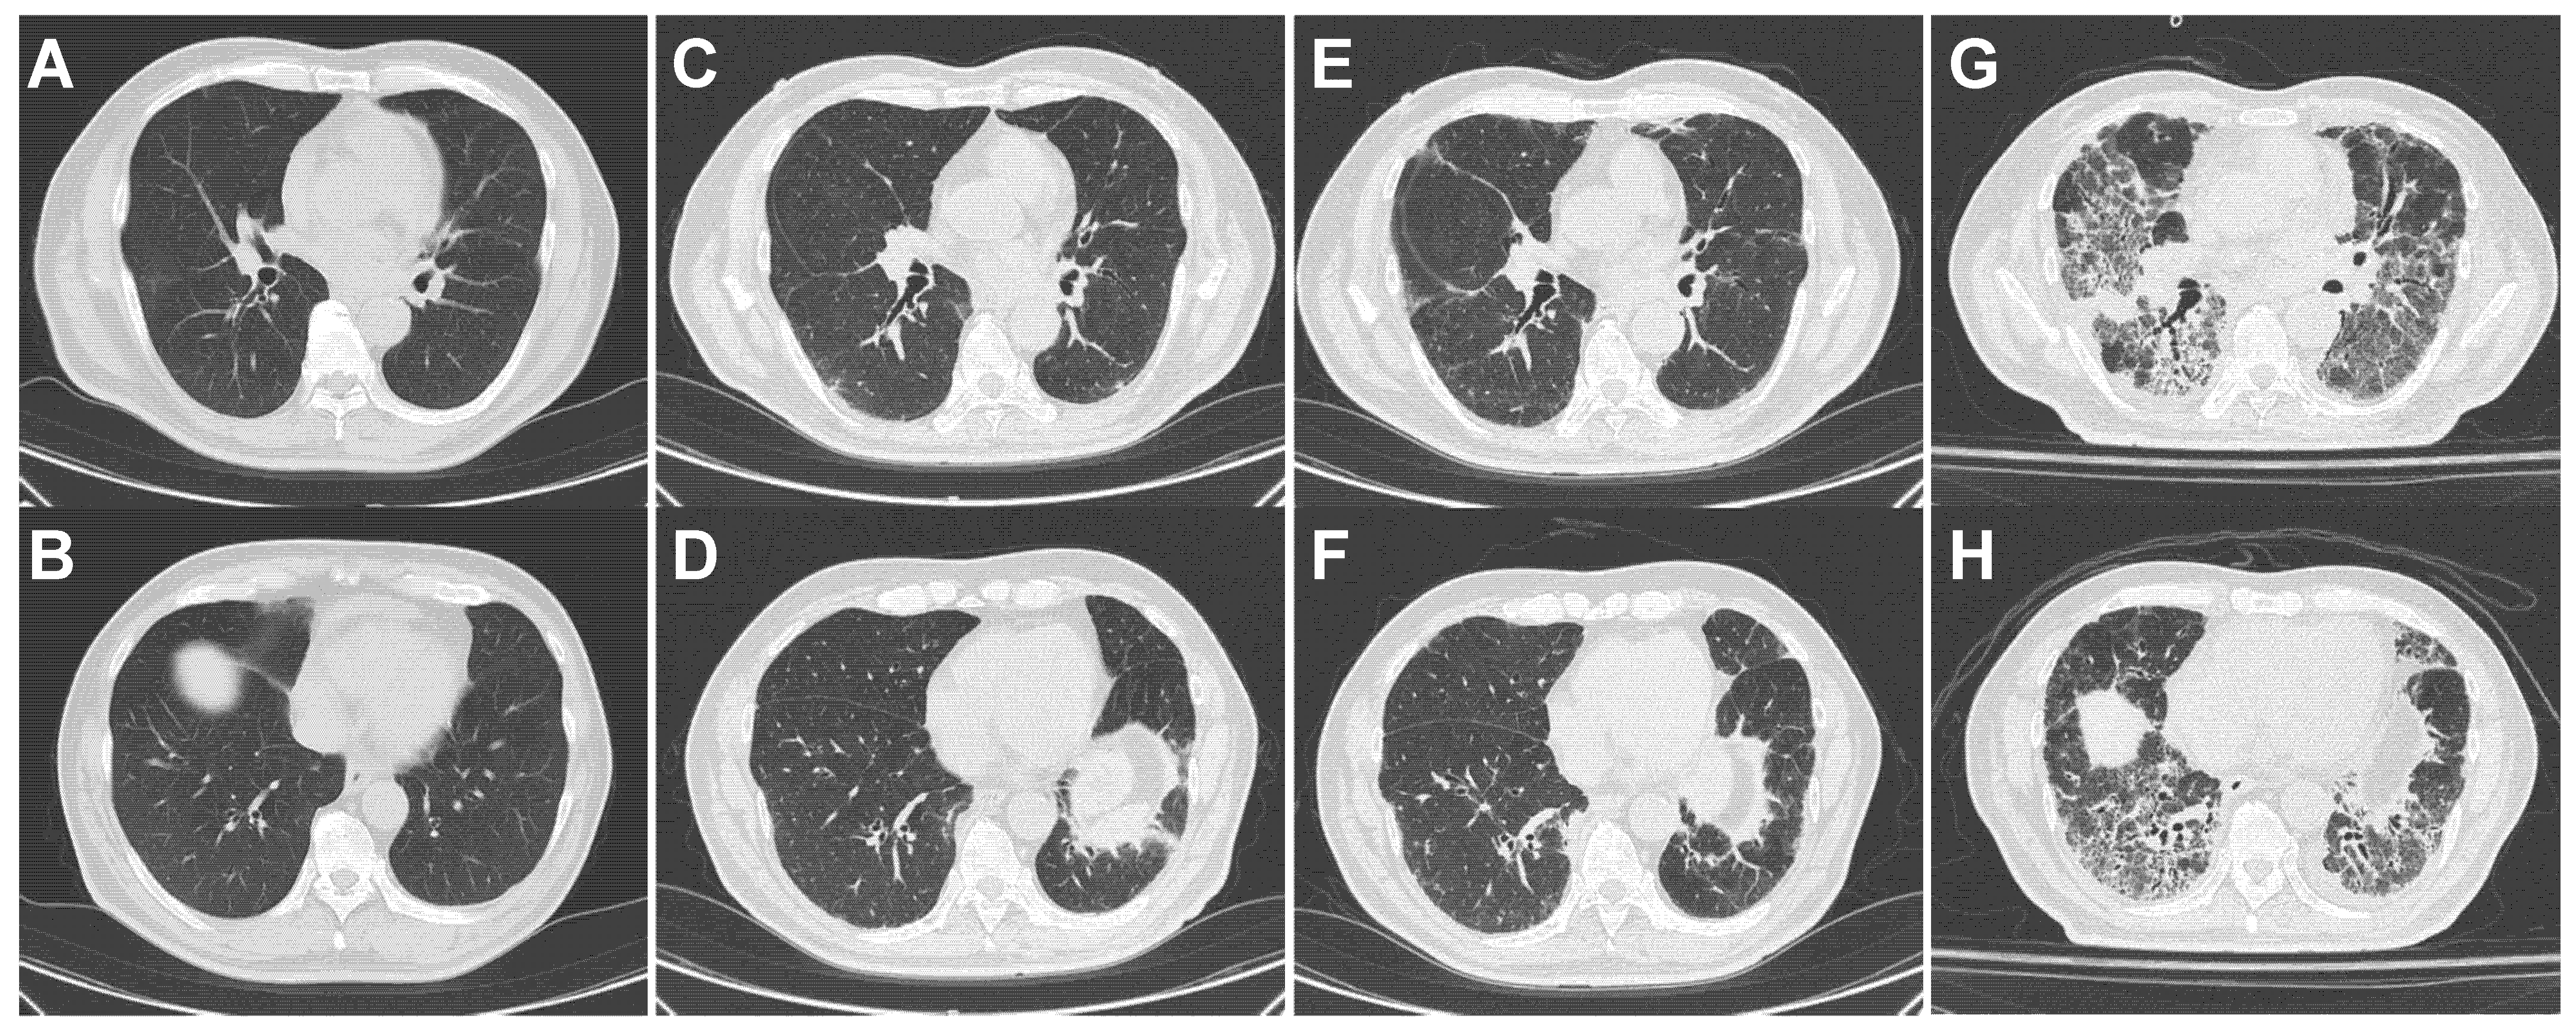

4.4.2. Patient 2 (Figure 3, Table 4)

4.4.3. Patient 3 (Figure 4, Table 4)